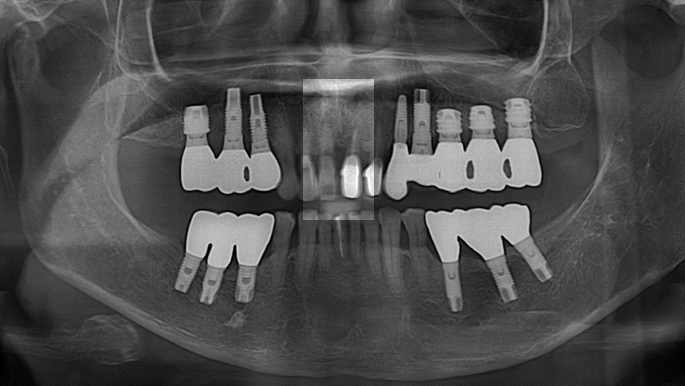

“Automated customized drilling protocols for optimum implant stability/ ONE-DAY implants ”

Clinical case: : Immediate loading of lower molars using R2Gate prefabricated 3D-printed provisional restoration

- Courtesy of Dr. Sam Omar, Egypt -